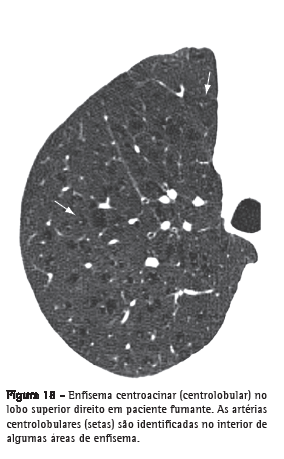

Enfisema centroacinar

Destruição das paredes dos alvéolos centroacinares, associada ao aumento dos bronquíolos respiratórios e dos alvéolos que se originam nesses bronquíolos. É a forma mais comum de enfisema em fumantes de cigarro. Os achados tomográficos são de áreas centrolobulares de diminuição da atenuação, usualmente sem paredes visíveis, com distribuição não uniforme, predominantemente localizadas nas regiões pulmonares superiores (Figura 18).(37,38) As artérias centrolobulares podem frequentemente ser identificadas no interior das áreas hipodensas. O termo centrolobular é comumente utilizado como sinônimo na TC.